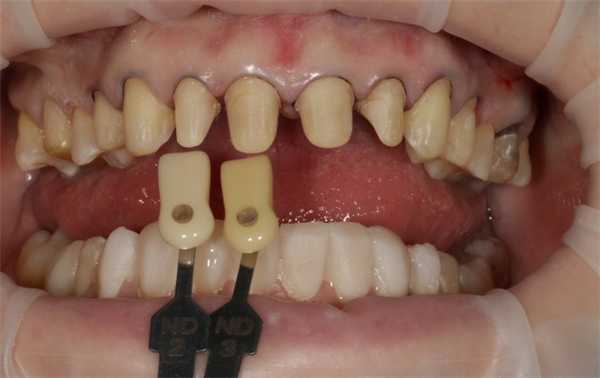

Определение цвета исходного зуба

На фото мы видим маркеры, необходимые определения подлежащих структур под керамическую реставрацию. В дальнейшем техник, ориентируясь на эти маркеры, создает искусственную культю зуба такого же цвета как у пациентки во рту, что дает возможность учитывать цветовые изменения на будущих керамических прозрачных конструкциях.

Сканирование внутри ротовым сканером, получения 3D объекта

Видим сканы того же препарирования, необходимые для изготовления керамических конструкций в CAD/CAM-программе.

После этого отправили сканы в лабораторию для изготовления керамических конструкций.